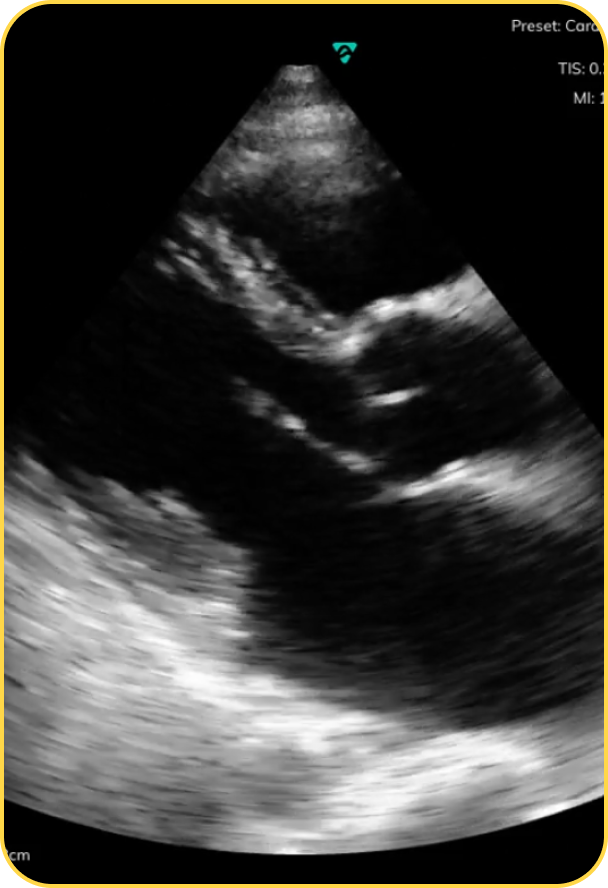

Real‑time imaging at the scene reveals internal bleeding, fluid around the heart, or a collapsed lung—helping clarify where the patient truly needs to go. Imaging changes destination decisions in 7.7% of cases.

See how Vave’s field‑ready ultrasound can help your crews make better triage, treatment, and destination decisions—from trauma and shock to cardiac arrest and respiratory emergencies.